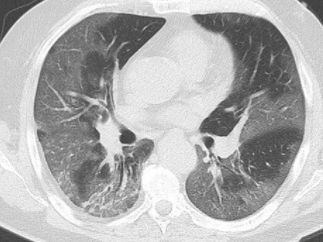

ここ1週間の大阪、1年前のCOVID-19パンデミック早期によく観察された、まりもみたいなOPパターンをすっ飛ばして「おしろいを塗りたくったような不気味な両肺すりガラス陰影」が大半です。初期は鼻カニュラでどうにか酸素化を維持できますが、この後浸潤影になり換気できる肺胞が急速に減少します。